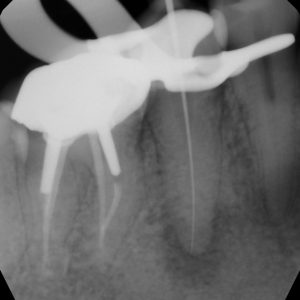

Root canal treatment

Sometimes, the nerve located inside the tooth becomes contaminated and reacts to this contamination. The intense pain that this contamination can cause is called pulpitis. Then the pulp (nerve of the tooth) breaks down and becomes infected. This is called pulp necrosis and is what causes dental abscesses. In either case, if you want to keep the tooth, it will be necessary to carry out root canal treatment. The dentist then removes what remains of the pulp, cleans and disinfects the canals of each of the roots and closes these canals with gutta percha (a material that looks like rubber). Following this procedure, it is possible to feel some discomfort which is generally treated well by taking Advil or Tylenol.